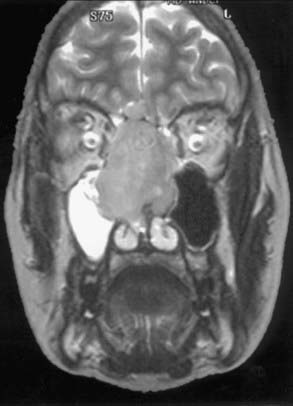

Esthésioneuroblastome

L’esthesioneuroblastome, également connu sous le nom de neuroblastome olfactif, est un cancer rare qui se manifeste dans le bulbe olfactive, la partie du cerveau qui interprète l’odeur. Les symptômes varient en fonction de l’emplacement et de l’étendue de la tumeur. Les symptômes les plus courants sont l’obstruction nasale, les saignements de nez, les maux de tête, les douleurs faciales et la diminution de l’odorat.

Les esthésioneuroblastomes sont traités chirurgicalement par chirurgie endoscopique endonasale et peuvent être suivis d’une radiothérapie ou d’une chimiothérapie.